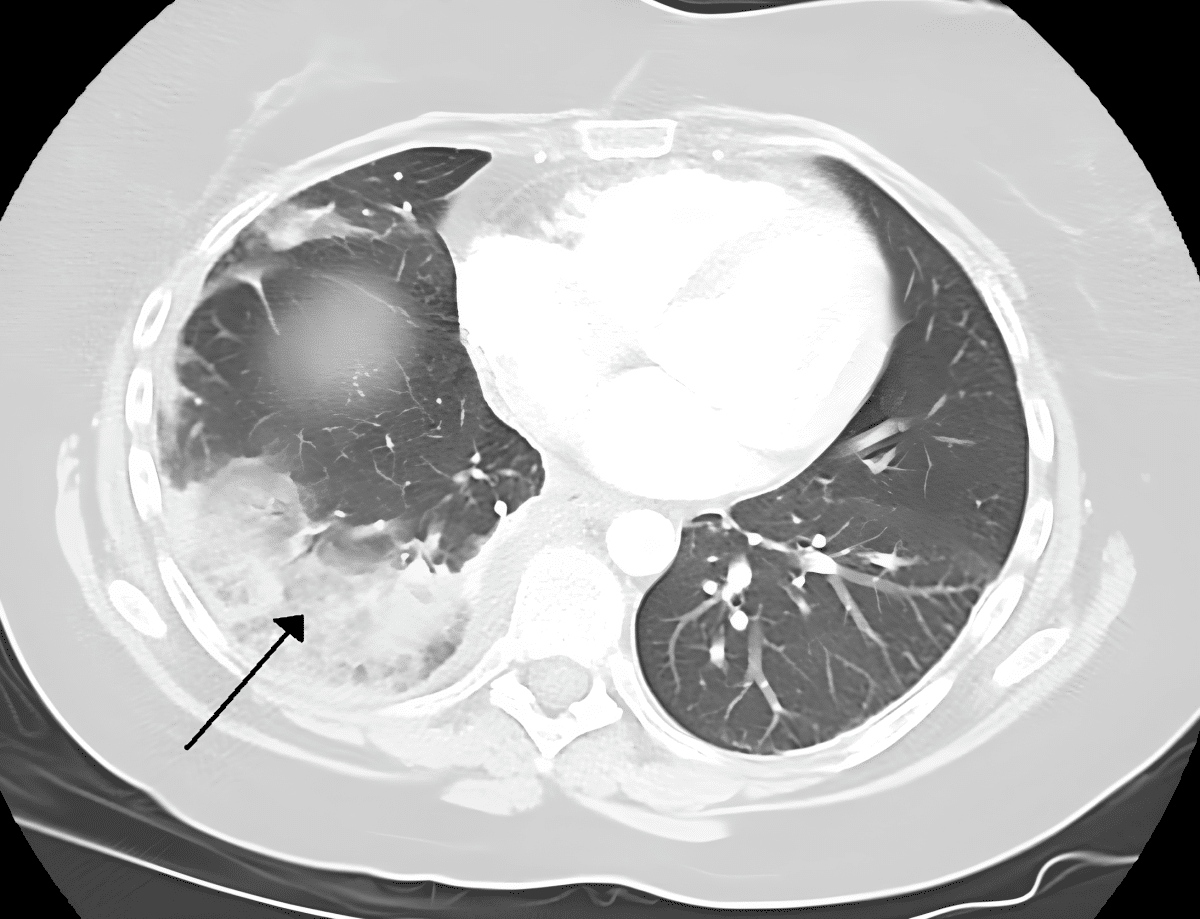

Одной из наиболее частых и серьезных осложнений после операций в торакальной хирургии является длительная утечка воздуха из легких. Традиционно для решения этой проблемы применяют биологический клей — так называемый герметик. Им фактически «заклеивают» дефекты легочной ткани. Но у существующих герметиков есть существенный недостаток — они недолговечны.

Для решения этой проблемы группа исследователей кафедры госпитальной хирургии №2 Сеченовского Университета предложила инновационный метод — комбинировать применение биологического клея с коллагеновой пластиной. Эффективность и безопасность нового метода уже успешно подтверждена на лабораторных животных. Предварительные результаты экспериментов показывают, что именно комбинированная методика на основе использования коллагеновой пластины значительно улучшает герметизацию легких и снижает риск послеоперационной утечки воздуха. Сейчас проект вышел на заключительный этап экспериментов на лабораторных животных.